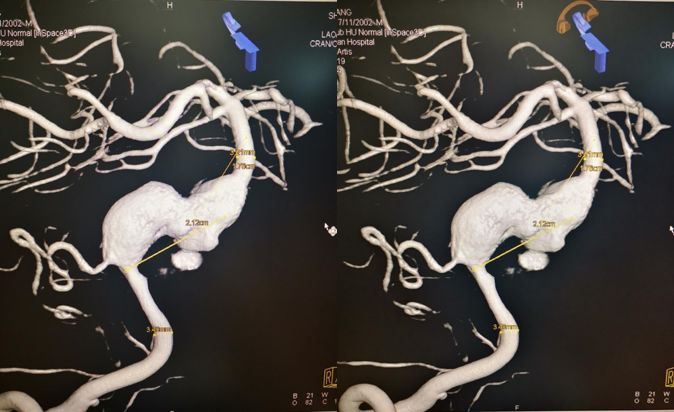

术前右椎动脉造影显示:基底动脉中下段夹层动脉瘤。

术前右椎动脉3D造影

术前左椎动脉造影显示:基底动脉中下段夹层动脉瘤,左侧小脑后下动脉夹层动脉瘤。

根据椎动脉3D造影测量结果,拟选择3.75 mm*35 mm的PED支架。